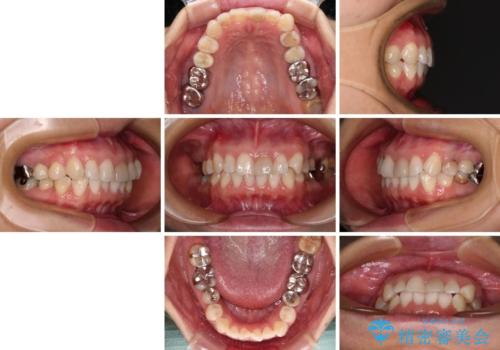

- 上下前歯のデコボコを気にして来院された患者様です。

カウンセリングにて詳しく話を聞いたところ、一番気になっているのは下顎前歯の叢生であり、上顎犬歯はあまり気になっていないとのことでした。

矯正治療は、歯の後戻りを抑制するために、治療終了後も保定装置をしっかりと使用していただくことが必須であるため、気になっている下顎だけを整えることで、その負担を半減できると考え、下顎のみの部分矯正として治療を行うこととしました。

装置としては、叢生の程度が強くなかったため、インビザラインの廉価版であるモデレート・パッケージを使用することとしました。